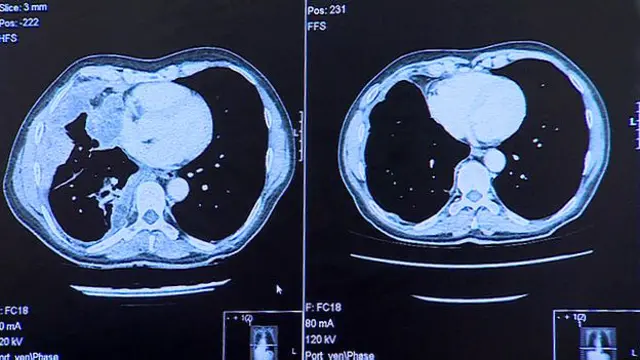

उनके फेफड़ों के स्कैन से पता चलता है कि तीन ख़ुराक के बाद ही इस दवा ने उनके फेफड़े से कैंसर को पूरी तरह ख़त्म कर दिया.